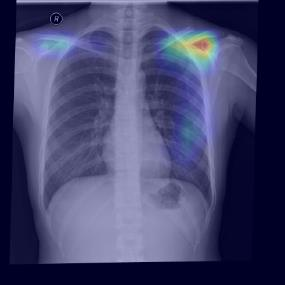

Chest X-ray (CXR) is the most typical diagnostic X-ray examination for screening various thoracic diseases. Automatically localizing lesions from CXR is promising for alleviating radiologists' reading burden. However, CXR datasets are often with massive image-level annotations and scarce lesion-level annotations, and more often, without annotations. Thus far, unifying different supervision granularities to develop thoracic disease detection algorithms has not been comprehensively addressed. In this paper, we present OXnet, the first deep omni-supervised thoracic disease detection network to our best knowledge that uses as much available supervision as possible for CXR diagnosis. We first introduce supervised learning via a one-stage detection model. Then, we inject a global classification head to the detection model and propose dual attention alignment to guide the global gradient to the local detection branch, which enables learning lesion detection from image-level annotations. We also impose intra-class compactness and inter-class separability with global prototype alignment to further enhance the global information learning. Moreover, we leverage a soft focal loss to distill the soft pseudo-labels of unlabeled data generated by a teacher model. Extensive experiments on a large-scale chest X-ray dataset show the proposed OXnet outperforms competitive methods with significant margins. Further, we investigate omni-supervision under various annotation granularities and corroborate OXnet is a promising choice to mitigate the plight of annotation shortage for medical image diagnosis.